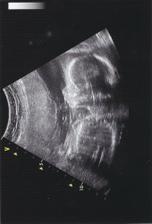

9.10.2007 - jedeme na vyšetření plodové vody do Gennetu

30.10.2007 - ultrazvuk v Gennetu, maličká je v pořádku a menší jen o týden